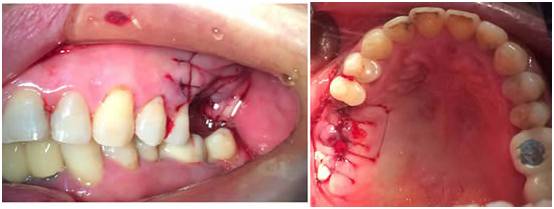

图二:术前准备口内照

图四:已经种好并缝合好了